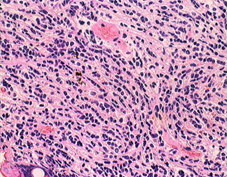

左は1歳児に発生した一部に神経芽細胞腫様の分化 row of the tumor cells (or neuronal differentiation) を伴う髄芽腫 medulloblastoma with extensive nodularity(小脳神経芽細胞腫 cerebellar neuroblastomaともいわれたもの)。右は7歳児の退形成(核の異形成)が顕著な退形成性髄芽腫 anaplastic medulloblastomaです。前者の治癒率は高く,後者の病理像の治癒率は極めて低いものです。